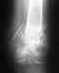

Порез был глубокий, заживало долго. Смотрели травматолог и два хирурга. Компрессы, мазь, укол в сустав. Через полтора года после травмы сустав снова сильно воспалился. Чем было спровоцировано непонятно.Два месяца ограниченная подвижность (палец до упора не сгибается), отек, болезненность при прикосновении, покраснение.Смотрели хирург, ревматолог.Противовоспалительные компрессы, таблетки, мази, электрофорез. Эффект небольшой. Есть 2 рентгеновских снимка (сразу после травмы и недавний). Заключение в прикрепленном файле.Екатеринбург, уралмашевская поликлиника. 53 года. Кроме этого, жалоб на суставы нет. Палец постоянно нагружен - основная работа на компьютере. Вопросы: - Лечит ли в УНИИТО такие суставы? Если да, то к какому специалисту лучше обратиться?- Кто в городе специализируется на суставах кисти?- Есть ли смысл делать МРТ кисти? УЗИ? И уже с ними идти на консультацию.